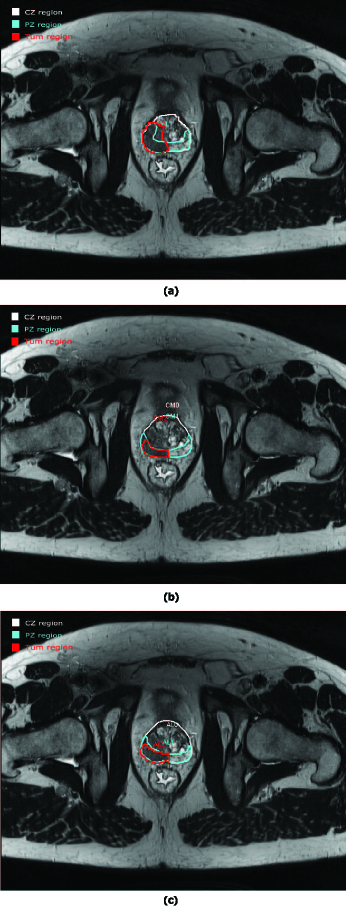

Refer to caption

Figure 2: Example of a prostate study evaluation from (a) E1 and (b) E2 with a discordance between both drawings for the tumour area. (c) New evaluation of the prostate study from E3 with a good agreement for the tumour area between E3𝐸3E3 and E2𝐸2E2.

Two examples of a PCa analysis are presented in Figures 1 and 2. The left image in Figure 1 corresponds to the drawing by the first expert (E1)𝐸1(E1) and in the right image by the second expert (E2)𝐸2(E2). Three ROIs are drawn in both images corresponding to CZ (white), PZ (blue) and Tumour (red). When visually comparing the two drawings, a very good concordance between CZ and PZ areas can be observed. Concerning the tumourous area, a small deviation is found but contours could be considered as relativity close between the two experiments.

However, not all the prostate studies were evaluated with such as good concordance between experiments. An example of discordance is shown in Figure 2. CZ and PZ have a good correspondence between E1𝐸1E1 and E2𝐸2E2 but an important discordance is observed for the tumour area. Then, a new evaluation of a prostate study for E3𝐸3E3 concerning the tumour area is shown in Figure 2 (c). In this example, we see the real advantage of collaborative work. According to the two experts after adjustments, the tumour area is similar.